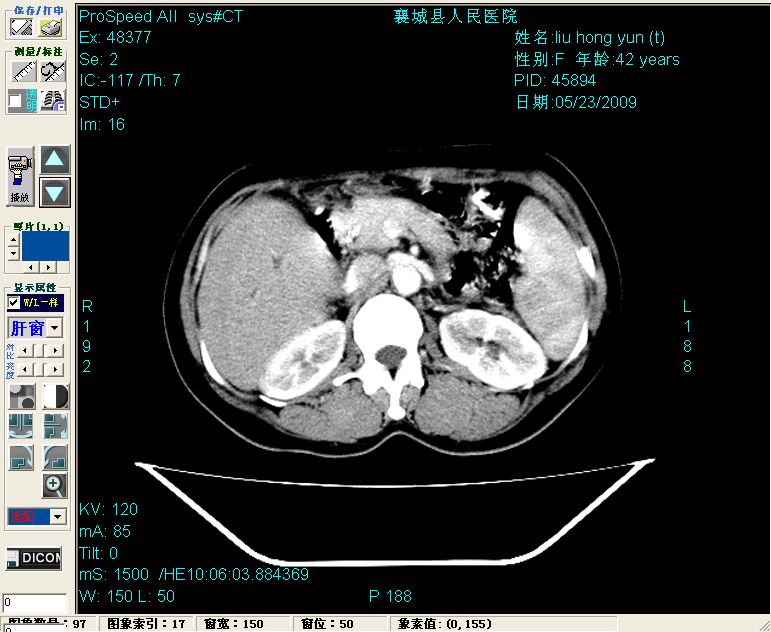

增强:

增强动脉期前述低密度区轻度早其强化,门脉期强化程度显著增高,延期扫描强化程度下降,但仍为相对高密度影

2左肝及右肝前叶表现考虑胆囊摘除术后所致的肝动门脉瘘形成,慢性纤维组织炎性增生.不完全除外左肝胆管细胞癌

1)肝内胆管结石,胆总管末端结石伴肝内胆管扩张。2)肝左叶及肝右叶前段增强前后之异常表现,考虑炎性改变,不排除胆管细胞癌。